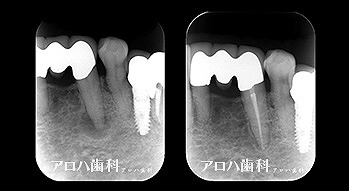

case4

再根管治療 2年予後

破折器具除去もあり

再根管治療の汚染の改善